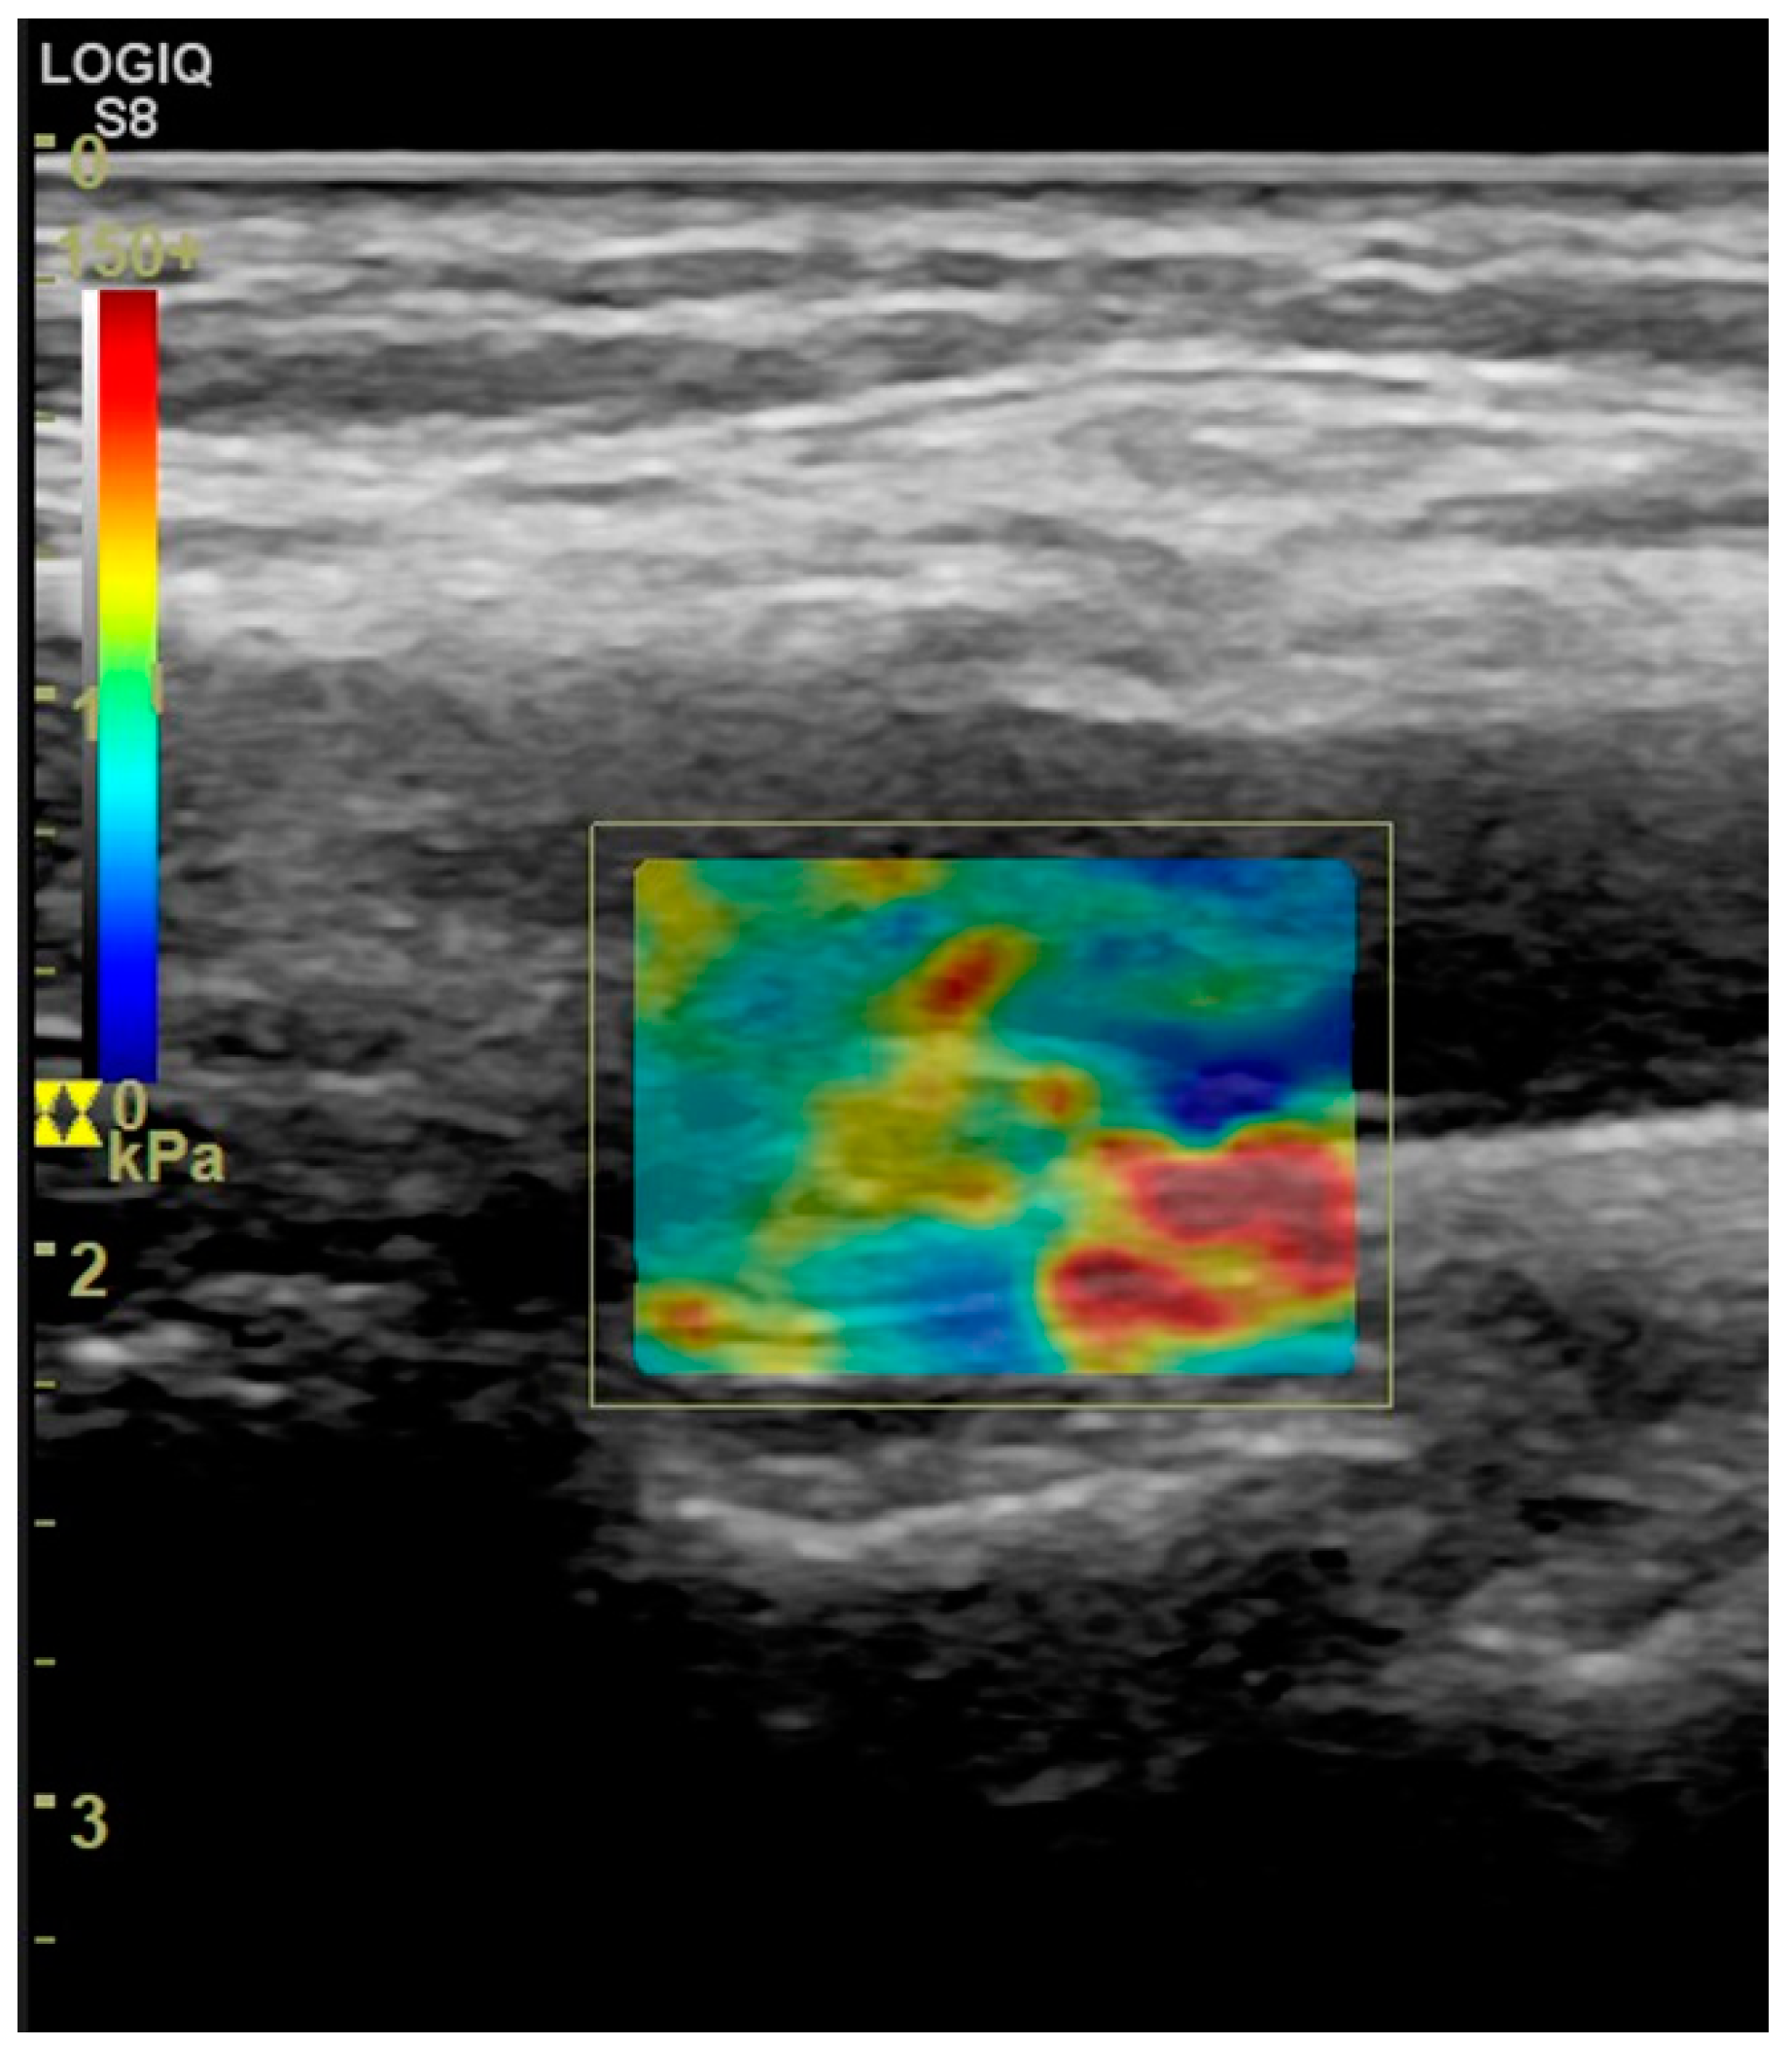

5. Elastography of Carotid Atherosclerotic Disease

- Di Leo, N.; Venturini, L.; de Soccio, V.; Forte, V.; Lucchetti, P.; Cerone, G.; Alagna, G.; Caratozzolo, M.; Messineo, D.; Di Gioia, C.; et al. Multiparametric ultrasound evaluation with CEUS and shear wave elastography for carotid plaque risk stratification. J. Ultrasound 2018, 21, 293–300. [Google Scholar] [CrossRef]

- Liu, F.; Yong, Q.; Zhang, Q.; Liu, P.; Yang, Y. Real-Time Tissue Elastography for the Detection of Vulnerable Carotid Plaques in Patients Undergoing Endarterectomy: A Pilot Study. Ultrasound Med. Biol. 2015, 41, 705–712. [Google Scholar] [CrossRef]

- Lou, Z.; Yang, J.; Tang, L.; Jin, Y.; Zhang, J.; Liu, C.; Li, Q. Shear Wave Elastography Imaging for the Features of Symptomatic Carotid Plaques: A Feasibility Study. J. Ultrasound Med. 2017, 36, 1213–1223. [Google Scholar] [CrossRef]

- Ramnarine, K.V.; Garrard, J.W.; Kanber, B.; Nduwayo, S.; Hartshorne, T.C.; Robinson, T.G. Shear wave elastography imaging of carotid plaques: Feasible, reproducible and of clinical potential. Cardiovasc. Ultrasound 2014, 12, 49. [Google Scholar] [CrossRef]

- Garrard, J.W.; Ummur, P.; Nduwayo, S.; Kanber, B.; Hartshorne, T.C.; West, K.P.; Moore, D.; Robinson, T.G.; Ramnarine, K.V. Shear Wave Elastography May Be Superior to Greyscale Median for the Identification of Carotid Plaque Vulnerability: A Comparison with Histology. Ultraschall Med. 2015, 36, 386–390. [Google Scholar] [CrossRef]